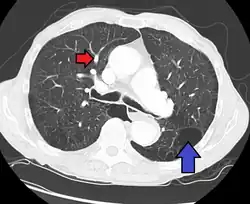

Hipertensão pulmonar visível por vasos excessivamente dilatados (seta vermelha) associado a enfisema pulmonar (seta azul)

Uma avaliação diagnostica completa inclui uma historia, exame físico, radiografia de tórax, provas de função pulmonar, eletrocardiograma (ECG), ecocardiograma, imageamento de ventilação perfusão e cateterismo cardíaco. Em alguns casos, pode ser necessária uma biopsia pulmonar, realizada por toracoscopia, visando elaborar um diagnóstico definitivo. O cateterismo cardíaco do lado direito do coração revela a pressão arterial pulmonar elevada. Um ecocardiograma pode avaliar a progressão da doença e excluir outras condições com sinais e sintomas similares.